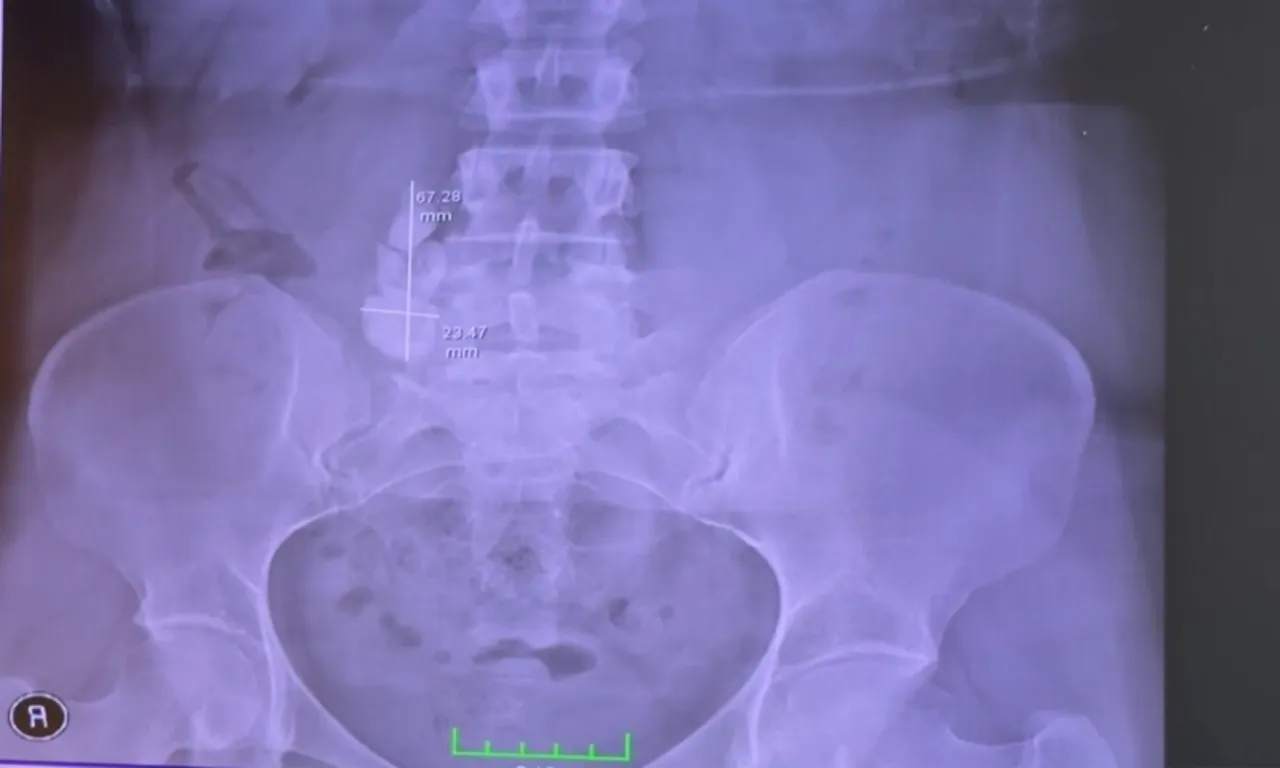

ÇEKİLEN FİLMLERDE ORTAYA ÇIKMADI

Özkaya, radyolojik görüntülerde bu kadar taşın görülmediğini, hastanın üreter kanalını açınca taş yoğunluğuyla karşılaştıklarını dile getirdi.

Mide bulantısı, ağrı ve sancıları nedeniyle sürekli hastaneye gittiğini anlatan Özer, "Her gün acile gidiyordum, ağrı kesici iğneler yaptırıyordum. Ameliyat oldum, ağrılarım geçti. Fatih hocaya çok teşekkür ederim. Filmlerde bu kadar taş görülmüyordu. Taşları görünce Fatih hoca da biz de çok şaşırdık" ifadelerini kullandı.